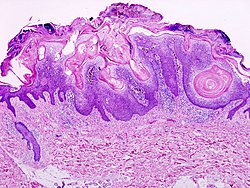

A. Pseudoepitheliomatous hyperplasia seemingly forms a dermal mass. B. Parakeratosis tops epidermis. C. Neutrophils lie in the center of the apparent mass. D. Diagnostic xanthoma cells lie in dermal papillae.